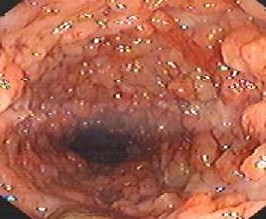

溃疡性结肠炎的常见体征

溃疡性结肠炎的常见体征有哪些?

诊断肠道疾病,北京丰益肛肠医院率先引进的超细无痛“高科技电子结肠镜检查仪”,该仪器集观察、诊断及治疗功能于一身,能直接观察肠道黏膜病变,尤其对细小病变的检查更精确,可对小的病变和炎性息内、癌前病变和早期肠癌进行观察和准确诊断;而且可以在镜下直接病灶给药,疗效显著。